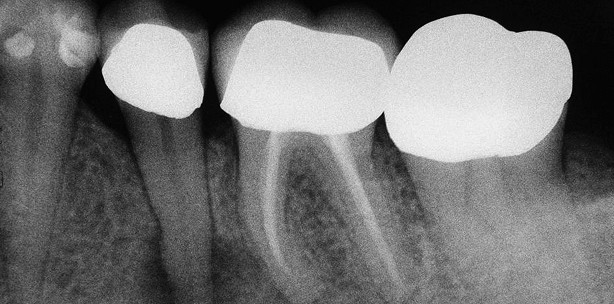

Ähnlich wie gerade beschrieben, konsultierte mich eine Patientin wegen starker Beschwerden im Unterkiefer links (siehe Abbildungen). Der Zahn 35 war sowohl klinisch durch Aufbissbeschwerden als auch röntgenologisch durch eine etwa erbsengroße apikale Aufhellung schnell als Ursache identifiziert und diagnostiziert (Abb. 1). Er wurde trepaniert und nach Anfertigung einer Messaufnahme (Abb. 2) aufbereitet und mit Natriumhypochloridlösung gespült. Nach Trocknung des Kanals behandelte ich diesen mit dem SIROLaser Advance. Eine Woche später erfolgte im Rahmen einer medizinischen Einlage eine weitere Behandlung mit dem Diodenlaser. Zu dieser Zeit waren die Beschwerden der Patientin deutlich reduziert und der Zahn nicht mehr aufbissempfindlich. In der nächsten Sitzung konnte der Zahn unter erneuter Laseranwendung abgefüllt werden (Abb. 3). Die Kontrollaufnahme 18 Monate später zeigt einen vollständigen Rückgang der apikalen Ostitis (Abb. 4). Erfolgserlebnisse wie diese sind durchaus keine Einzelfälle. Bei der konventionellen Wurzelkanalbehandlung unter Anwendung von Spülflüssigkeiten wird meistens nur eine Keimreduktion im Hauptkanal erreicht. Keime im Bereich des apikalen Deltas sowie um die Wurzelspitze herum persistieren jedoch. Bei Anwendung des Lasers wird eine bakterizide Wirkung auch im periapikalen Gewebe und den Nebenkanälchen erreicht. Dies erklärt die Erfolge auch bei aussichtslos erscheinenden endodontischen Fällen. So konnte ich beispielsweise im Rahmen einer meiner letzten Urlaubsvertretungen mit Unterstützung des SIROLaser Advance eine Patientin mit dicker Backe und reichlich Pusaustritt nach Trepanation in drei Sitzungen ohne Antibiotikum und mit schnell einsetzender Beschwerdefreiheit erfolgreich therapieren.